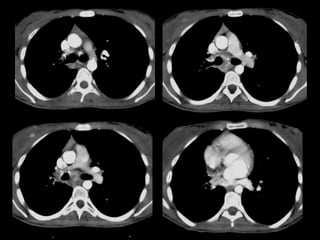

Mujer de 18 años con episodio de hemoptisis con

exploración ORL normal